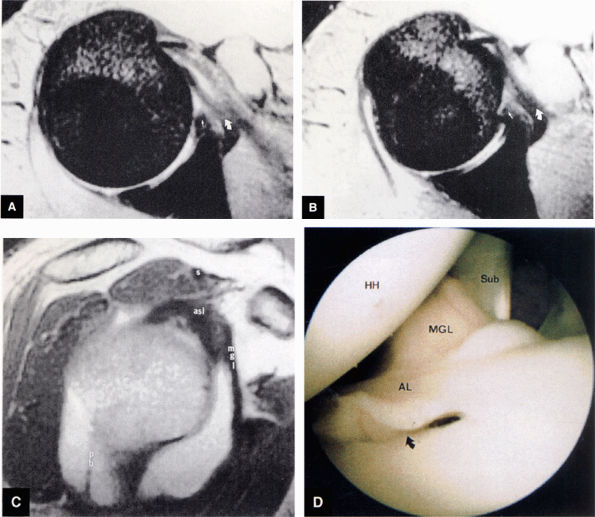

FIGURE 8.83 ● T2*-weighted axial images at (A) and below (B) the level of the subscapularis show the normal middle glenohumeral ligament (MGL; curved arrows), its medial origin from the glenoid and neck of the scapula, and its attachment to the lesser tuberosity. Small straight arrows, anterior labrum. (C) A T1-weighted sagittal oblique arthrogram shows the attachment of the MGL (mgl) to the anterior superior glenoid labrum (asl). The MGL arises from the labrum below the superior glenohumeral ligament and from the neck of the scapula. The humeral attachment of the MGL is located medial to the lesser tuberosity. Normal variants of the MGL include the ligament arising only from the labrum or having no attachment to it. pb, posterior band of IGL; s, supraspinatus tendon. (D) Arthroscopic view of the middle glenohumeral ligament (MGL) anterior to the anterior labrum (AL) and posterior to the subscapularis tendon (Sub). An anterior superior quadrant sublabral foramen (curved arrow) exists as a normal variant. HH, humeral head.